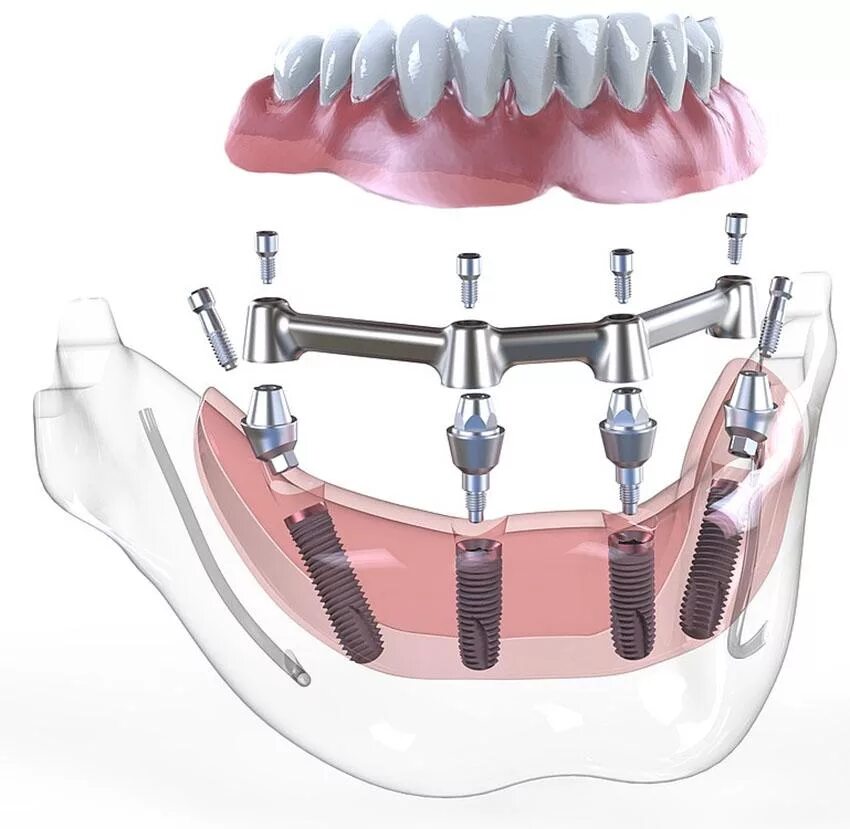

Поставить 4 зуба